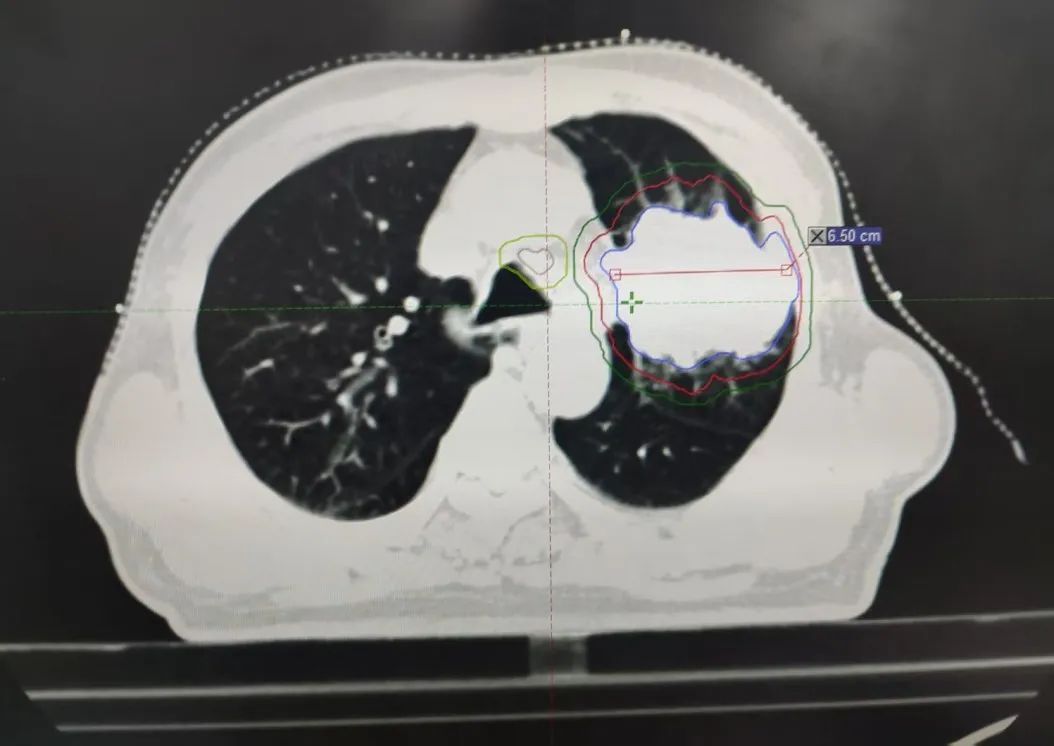

内容提要 PART. 01 高龄抗癌的“生死抉择” 当6.7cm肿瘤遇上80岁身体 四年前,李大爷因乏力、消瘦、气短等症状,意外发现左肺巨大占位,大小约6.7cm×4.9cm,最终在北京大学肿瘤医院确诊为肺鳞癌。面对82岁高龄和肿瘤的凶猛进展,家属一度陷入绝望,并决定回到家乡医院寻求治疗方法。 治疗前肿瘤影像 “开胸手术风险极高,传统化疗对肺鳞癌效果有限,还可能加重身体负担。”王春强主任回忆,团队当即决定采用局部精准放疗,在确保疗效的同时,最大限度减少对正常组织的损伤,提高生活质量,为老人开辟一条生路。 PART. 02 四年抗癌“成绩单” 肿瘤缩小70%,生活如常 治疗的关键在于“毫米级”的精准打击。依托国内顶尖放疗设备——美国瓦里安直线加速器,团队通过三维适形调强放疗技术(IMRT),将放射线误差控制在1mm内,既集中火力攻击肿瘤,又能降低周围肺组织损伤。配合PET/CT生物靶区动态追踪技术,医生能清晰区分活跃癌细胞与坏死组织,实时调整治疗方案。 四年间,李大爷的肿瘤病灶持续缩小,从最初的6.7cm缩小至目前的2.3cm,气短症状显著改善,治疗期间甚至未出现放射性肺炎等并发症。如今的他不仅生活完全自理,还活跃于社区老年活动,焦虑评分从重度降至几乎消失。 治疗后肿瘤影像 “很多患者以为抗癌就是‘你死我活’,其实‘带瘤生存’同样能创造生命价值。”这场“生命奇迹”的背后,是市二院放射治疗中心对精准医学的深刻践行,科室凭借超高的技术水平及一批国际顶尖设备支持,不断提升生物靶区勾画精度,并建立多学科诊疗(MDT)模式,融合外科、靶向、免疫、粒子等手段,为200余例高龄肿瘤患者制定个性化方案,颠覆了“高龄癌症等于绝症”的传统认知。 PART. 03 人民医院 人民名医 王春强 副主任医师 ·葫芦岛市第二人民医院放射治疗中心主任 ·原中国人民解放军第255医院放射治疗组组长 ·天津市第五中心医院放射治疗科主治医师 ·中国抗癌协会会员 ·中国医学继续教育协会肿瘤放射治疗专业委员 ·中国老年保健协会免疫健康管理专业委员会委员 ·中国老年保健协会多学科诊疗专业委员会委员 ·辽宁省免疫学会肿瘤营养与免疫分会委员会委员 专业特色: 从事肿瘤放射治疗近20年,曾于空军总医院进修肿瘤放射治疗学。擅长头颈部肿瘤、胸腹部肿瘤、盆腔肿瘤等肿瘤多发、疑难病诊治。精通三维适形放射治疗(3DCRT)、调强放射治疗(IMRT)、图像引导放射治疗(IGRT)、容积旋转调强放射治疗(Rapid-Arc)、SBRT、VMAT等先进放疗技术。尤其擅长中枢神经系统肿瘤、鼻咽癌、宫颈癌、直肠癌、食管癌、肺癌、脑转移、骨转移、淋巴结转移、肺转移、肝转移等肿瘤的放疗,尤其对部分肿瘤的疑难杂症的处理积累了丰富的经验。熟练掌握头颈部及体部肿瘤的影像诊断及综合治疗原则,注重规范化治疗。擅长为肿瘤患者制定个体化治疗方案。